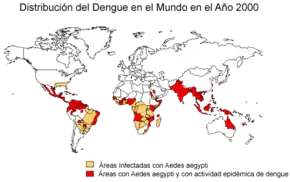

Es una infección muy extendida que se presenta en todas las regiones de clima tropical del planeta, y últimamente en regiones de clima templado con veranos cálidos y húmedos. En los últimos años la transmisión ha aumentado de manera predominante en zonas urbanas y se ha convertido en un importante problema de salud pública. En la actualidad, más de la mitad de la población mundial está en riesgo de contraer la enfermedad. La prevención y el control del dengue dependen exclusivamente de las medidas eficaces de lucha contra el vector transmisor, el mosquito.[4]

El número de casos de dengue ha aumentado dramáticamente desde la década de 1960. De acuerdo con la OMS, en las últimas dos décadas aumentó 8 veces más el número de casos notificados, con una estimación de entre 284 y 528 millones de personas infectadas anualmente.[5] Las primeras descripciones datan de 1779 y su causa viral y la transmisión fueron entendidas a principios del siglo XX. El dengue se ha convertido en un problema mundial desde la Segunda Guerra Mundial y es endémica en más de 110 países. Aparte de la eliminación de los mosquitos, se está trabajando en una vacuna contra el dengue, así como la medicación dirigida directamente al virus.

Epidemiología

La Organización Mundial de la Salud (OMS) estima que el número de afectados por dengue se encuentra entre los 100 millones y los 400 millones de personas cada año, con un total de medio millón que necesitan atención hospitalaria por presentar una forma grave de la enfermedad, con una mortalidad del 2,5 %.[cita requerida]

El dengue posee una extensión geográfica similar a la de la malaria (en países tropicales y subtropicales) pero a diferencia de esta, el dengue se encuentra en zonas urbanas.

El dengue se transmite a los humanos por el mosquito Aedes aegypti, el cual es el principal vector de la enfermedad en el hemisferio occidental, aunque también es transmitido por el Aedes albopictus.

Durante los años 2000, en Sudamérica se ha registrado el más dramático incremento de la incidencia del dengue, especialmente en Brasil, Colombia, Ecuador, Panamá Paraguay, Perú y Venezuela.[19]

Actualmente, en Venezuela se produce aproximadamente el 70 % de todos los casos en América, mientras que Colombia es donde se ha registrado el mayor número de casos de dengue hemorrágico y de casos fatales en los últimos años.[19]

En 2019 se registró la mayor cantidad de casos de dengue notificados a nivel mundial. Pasó de 0.5054 millones de casos (en 2000) a más de 2.4 millones (en 2010) y 5.2 millones (en 2019). Todas las regiones de la OMS se vieron afectadas y se registró por primera vez la transmisión del dengue en Afganistán.[23]